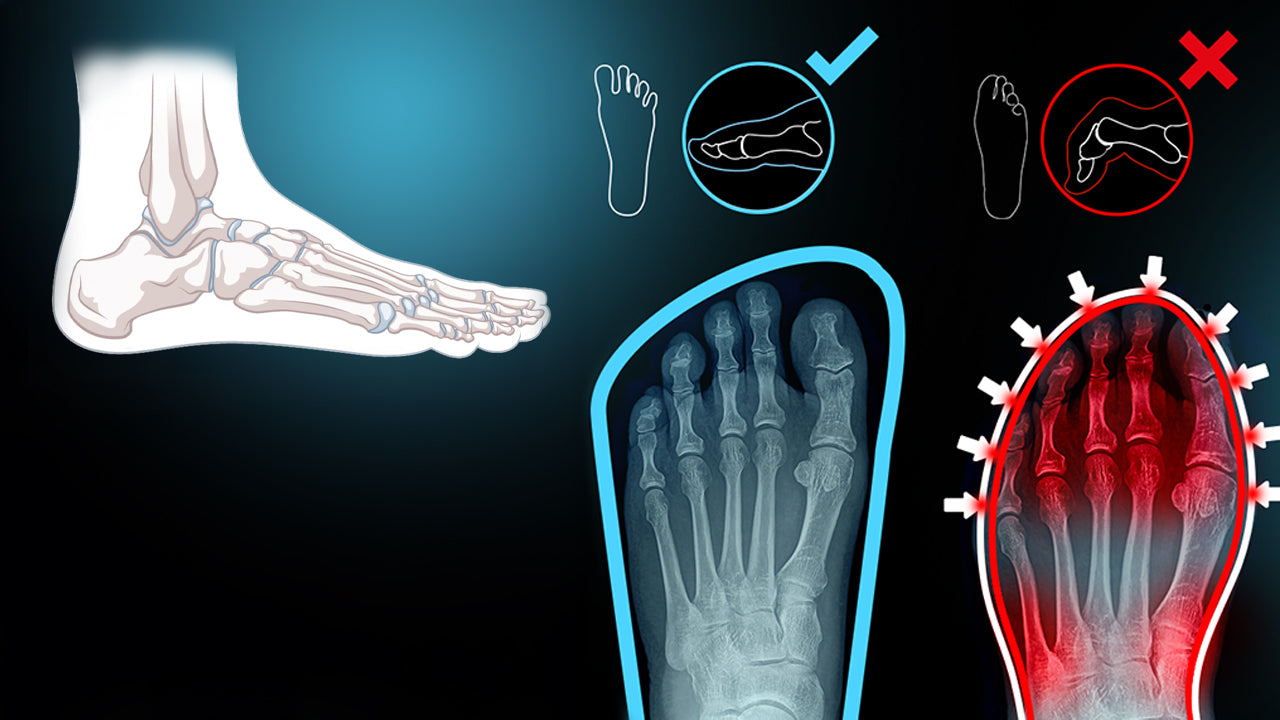

Warum mir nie jemand gesagt hat, dass meine Schuhe das Problem sind

Experten bestätigen, dass herkömmliche Schuhe die natürliche Biomechanik unserer Füße einschränken. Wenn wir in stabilen, festen Schuhen laufen, nehmen unsere Füße kaum Arbeit ab – und so landen die Belastungen bei den Knien, Hüften und dem Rücken.

Durch den Wechsel auf einen Schuh wie den Barfußschuh von Freiluftkind, der die natürliche Bewegung ermöglicht, kann die Muskulatur im Fuß wieder gestärkt werden. Dies führt langfristig zu einem gesünderen Gangbild und weniger Belastung für die Gelenke.